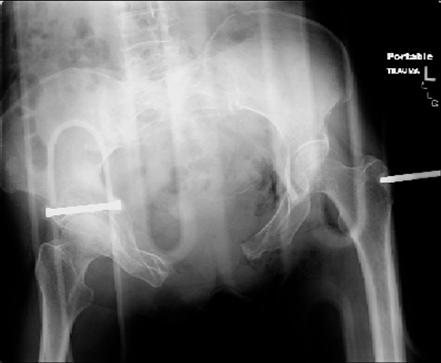

injuries are limited to the pelvis. left rami open and visible in a 10cm vertical laceration just lateral to left labia majora. wound is grossly clean. no vaginal and no urinary issues. CT scan shows widening of both SI joints anteriorly but I think this is vertically stable pattern.

pt treated that night with I/D and supra-acetabular frame to close the ring. consideration was given for SI screws bilateraly, but given time of night and other factors decision made not to proceed.

so the question is what next operatively if anything? concerns are infection, nonunion anteriorly and possible incompetence of the pelvic floor which may lead to prolapse issues. right rami are comminuted and plating may entail ilioinguinal approach to extend plate laterally to right iliac wing. retrograde screw up right rami is an option but I am not convinced it will add much. adding SI screws very doable, but major concern is restoring anterior ring. so far wound is clean and closed over a drain, and I have no plans to open it back up and wash again.